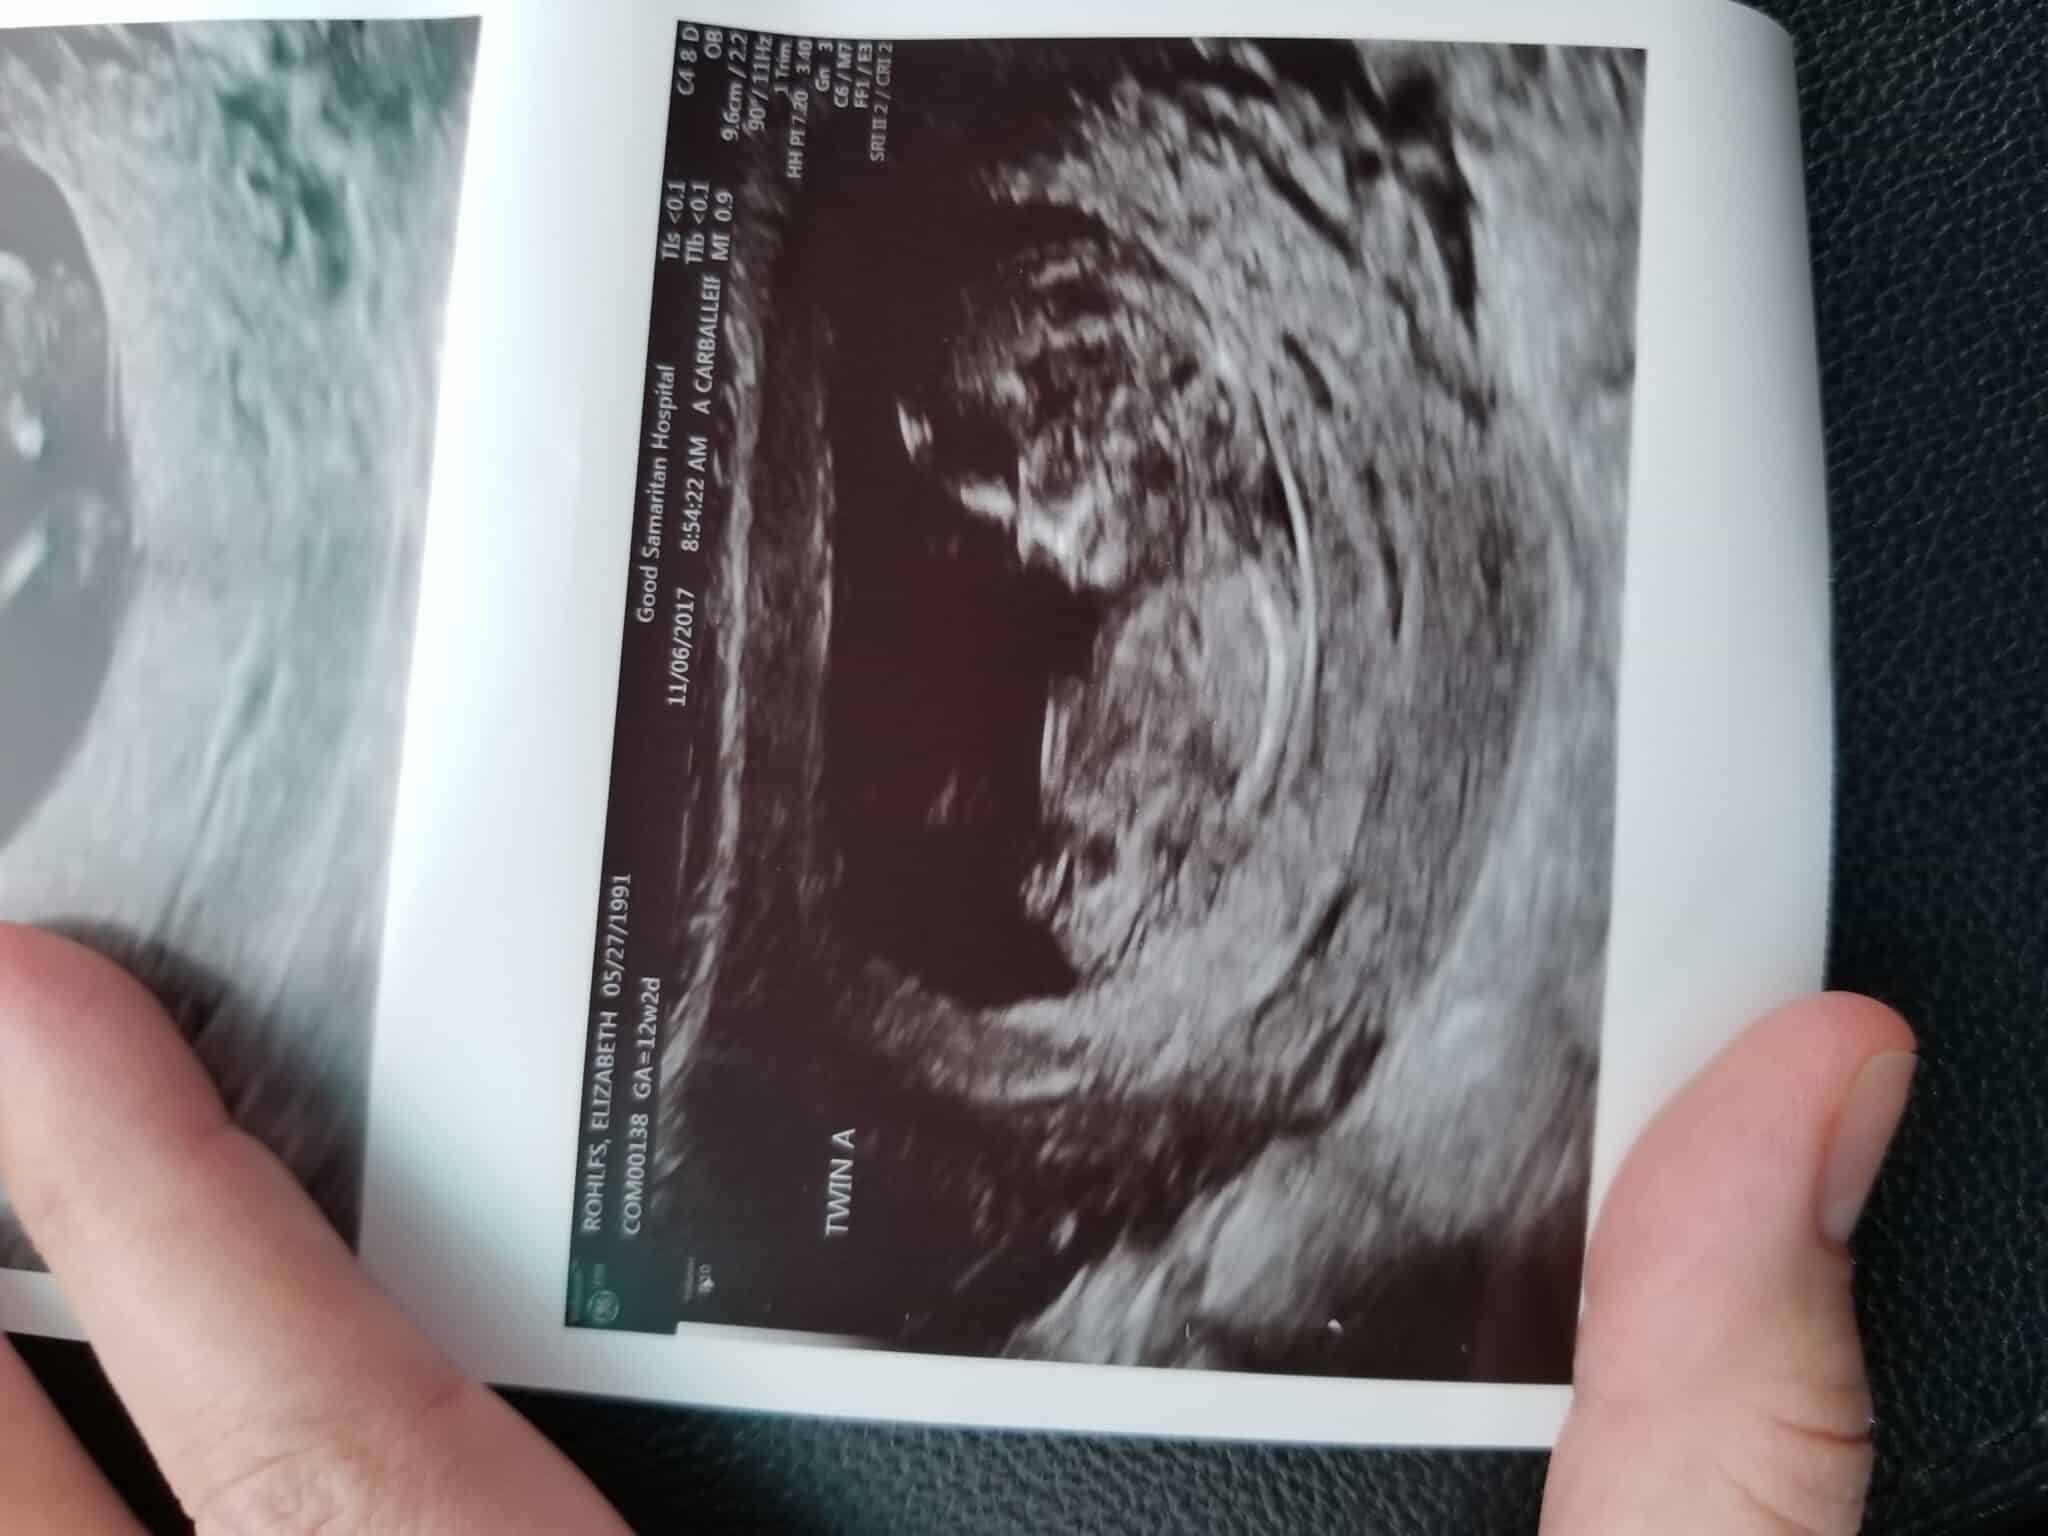

Ultrasound Photos at 12 Weeks Pregnant With Twins